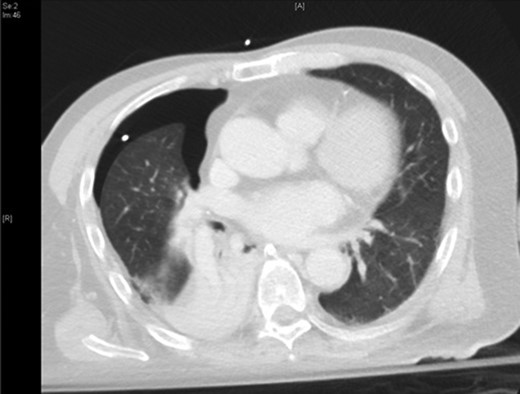

The patient was urgently reviewed by the cardiothoracic surgeons, and a small-bore chest tube was inserted, following which a computed tomography of the thorax was performed. This showed a residual but smaller pneumothorax with the chest tube in situ, associated with a small hemothorax (Fig. 3). Due to failure of conservative management and concern of a bronchopleural fistula resulting in air leak, he underwent explorative thoracoscopic surgery. Intraoperatively, an area of lung was noted with contusional changes and a bleb (Fig. 4), and a wedge resection of the right lower lobe was performed (Fig. 5). He made an uneventful recovery and was discharged.

Video assisted thoracoscopic surgery showing an area of right lung associated with a bleb and contusional changes.